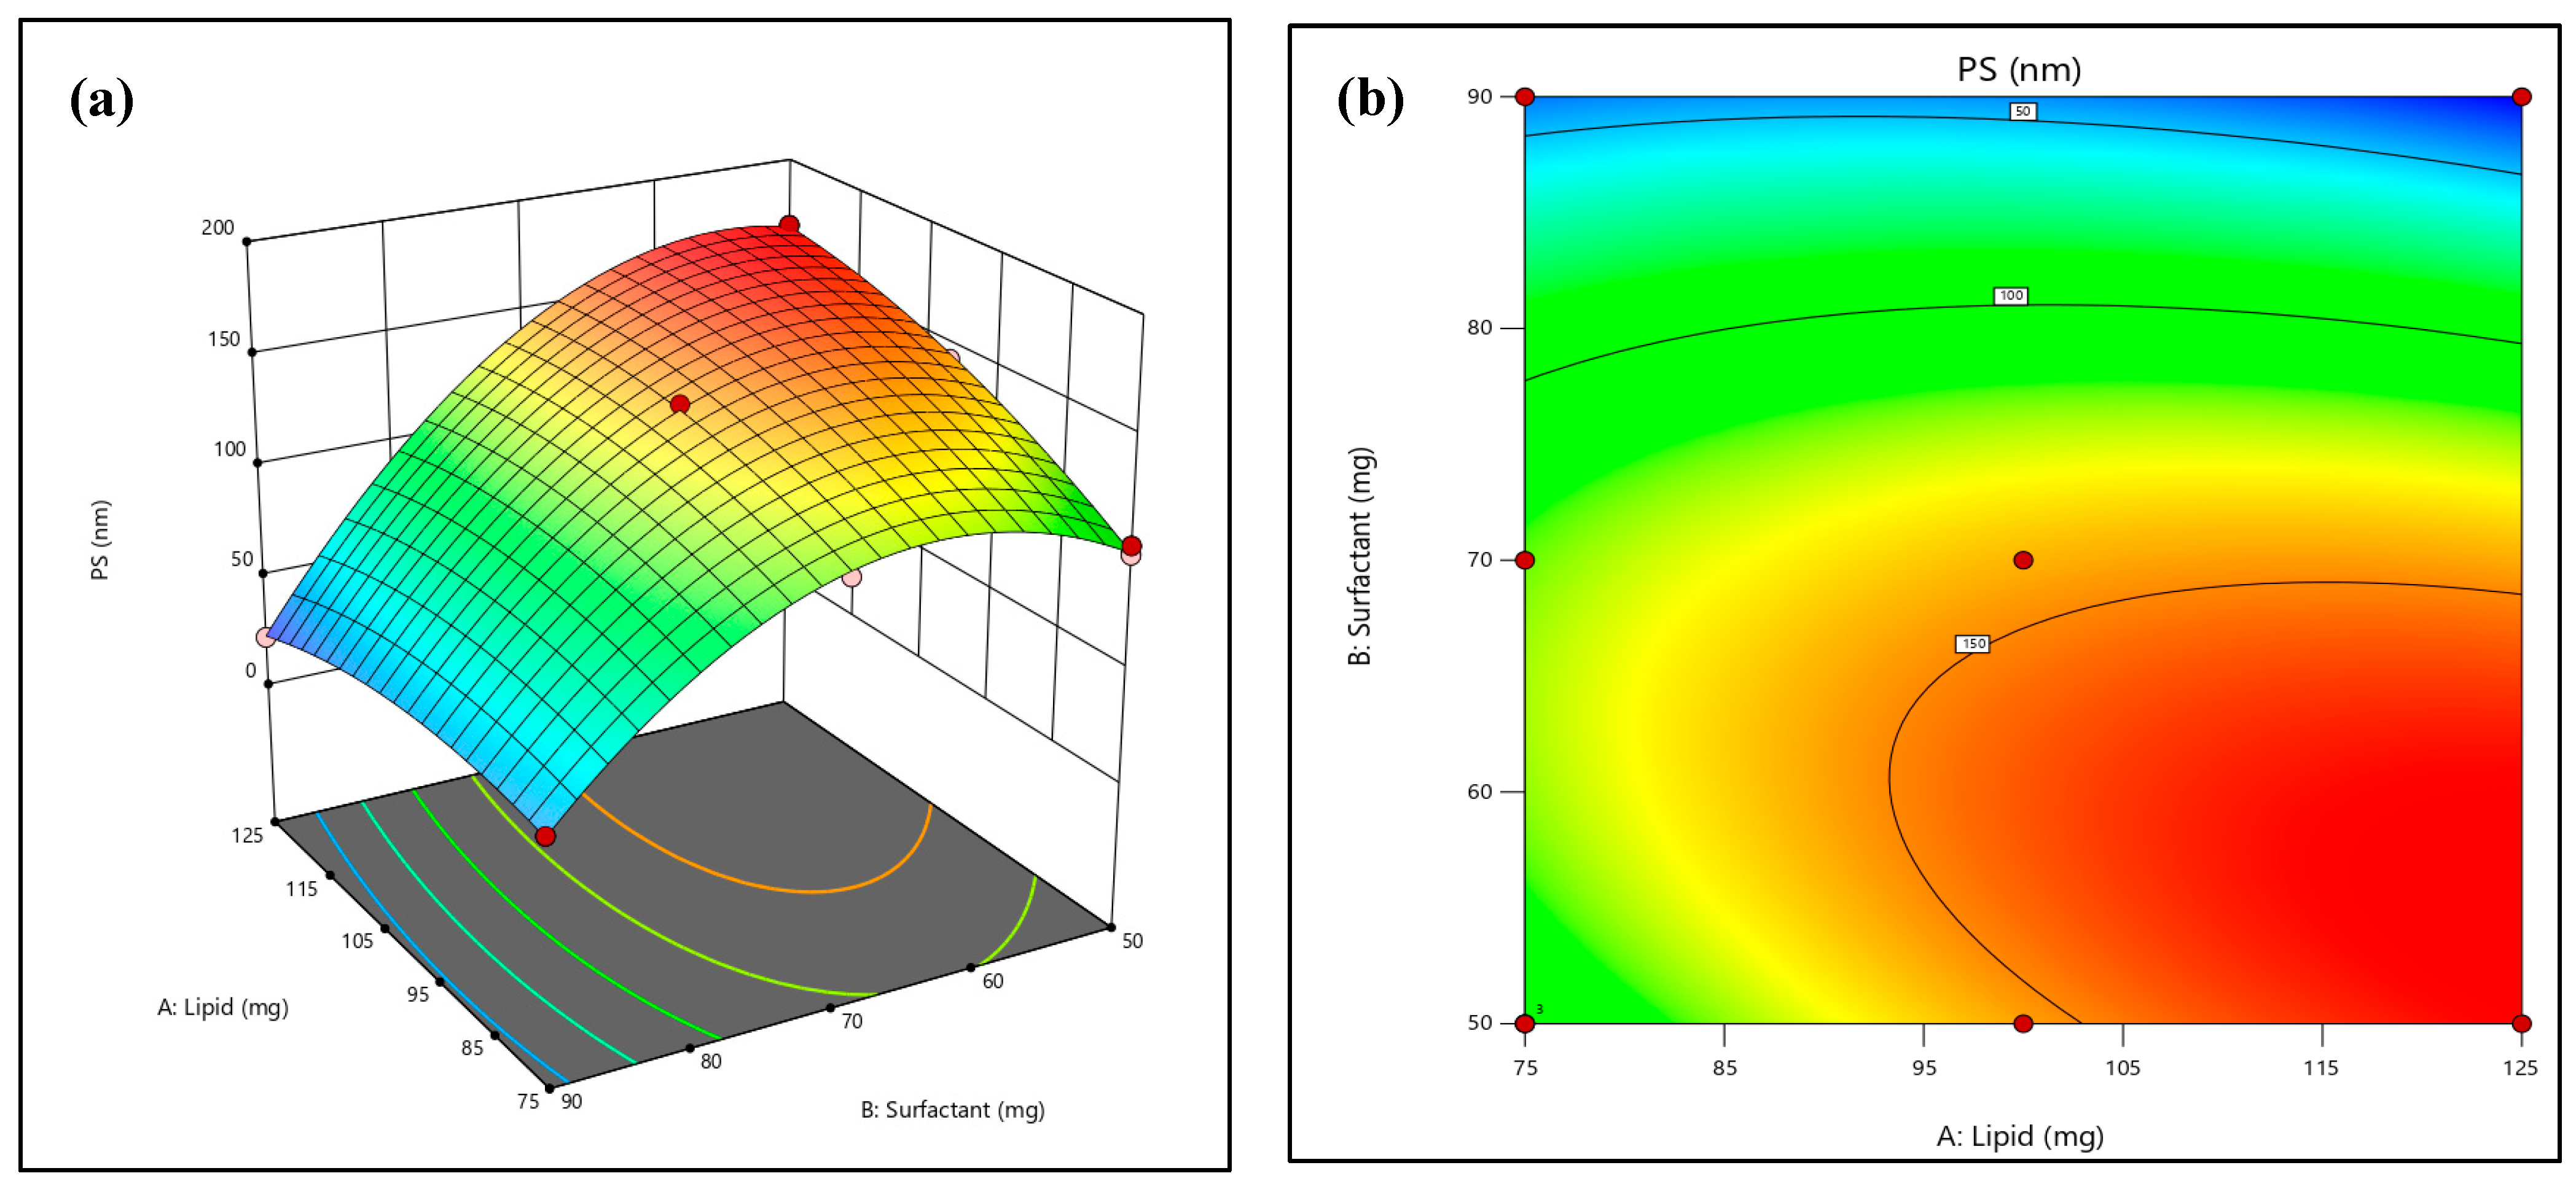

2.2. Effect on the Vesicles Size

2.3. Effect on Entrapment Efficiency

2.4. Optimization of Formulation

3.2.2. Experiment Design for Optimization

3.2.3. Optimization of the Formulation